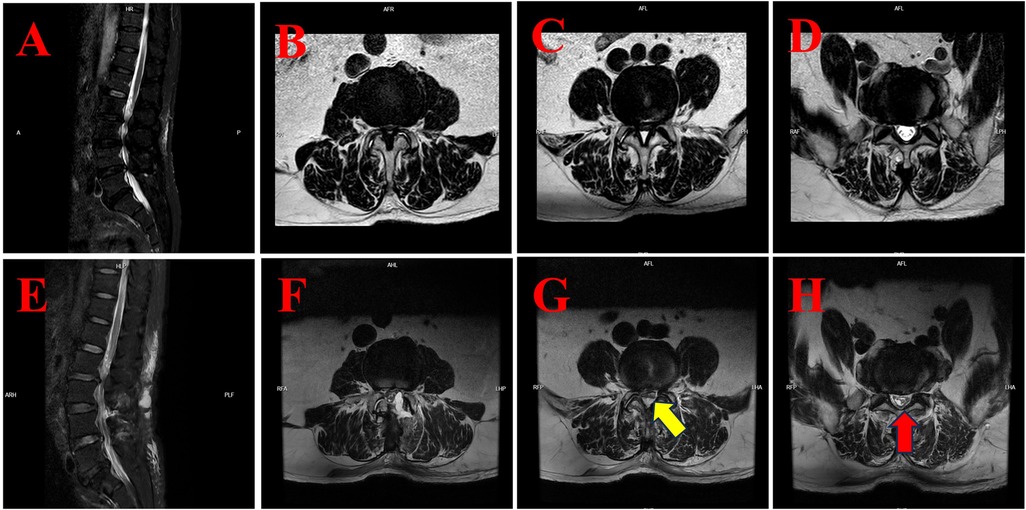

Background: Biportal Endoscopic Spinal Surgery (BESS) is a minimally invasive technique that has gained popularity for performing spinal procedures, including discectomy, decompression, and interbody fusion, in the cervical, thoracic, and lumbar regions. Whilst dural tears, epidural haematoma and transient paresthesia are well-documented complications associated with BESS, cases of subdural hygroma remain exceedingly rare. The present study presents a case series of three patients who developed postoperative subdural hygroma following BESS. An accompanying literature review was conducted in order to explore potential mechanisms and management strategies. Case Presentation:The initial case pertained to a 35-year-old male patient who underwent a cervical discectomy and foraminal decompression via BESS for the treatment of cervical spondylosis. Subsequently, the patient developed a cranial subdural hygroma. The second patient, a 53-year-old male, underwent a lumbar discectomy and decompression via BESS for lumbar disc herniation with concomitant spinal stenosis. Postoperative imaging revealed extensive lumbar subdural hygroma. The third case report concerns a 74-year-old male patient who underwent BESS decompression surgery for lumbar spinal stenosis. Postoperatively, the patient developed a subdural hygroma in the lower lumbar region. Conclusion: The development of subdural hygroma following BESS may be attributed to a combination of factors, including occult dural tears, abrupt alterations in intraspinal pressure, and ischemia-reperfusion injury. In view of the potential clinical implications of this rare complication, greater awareness and monitoring is warranted in the postoperative management of patients undergoing BESS.